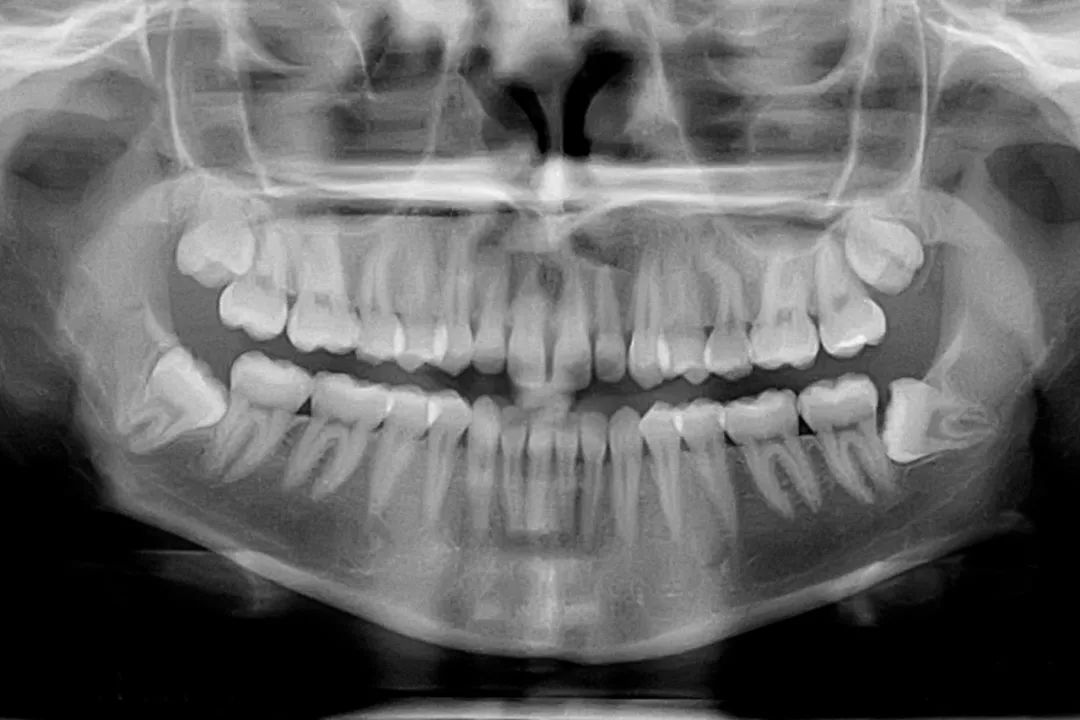

如今,在美国,拔除智齿几乎已经成为了一种传统。但是,从我的角度来看,这种“传统”的历史并不悠久。我是一名牙齿人类学家和进化生物学家,并且花了30年的时间研究当代人的牙齿和化石人类以及无数其他物种的牙齿。

我们目前常常见到的齿科问题并不正常。不仅大多数其他脊椎动物没有与我们相同的牙齿问题——他们很少有弯曲的牙齿或蛀牙;就连我们的化石前辈也没有影响生活的智齿,更是几乎没有牙龈疾病。

这些矛盾是新近才出现的,换言之,只是工业时代的当代人口才会有这些问题。最好的解释是如今的饮食与我们长久以来进化的牙齿和颌骨并不匹配。古生物学家早就知道,我们的牙齿植根于进化史中,现在,临床研究人员和牙科医生也开始注意这一事实。